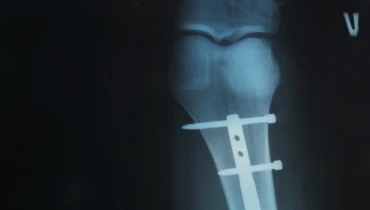

Остеосинтез штифтом – это внутренняя фиксация при нарушении целостности кости полым или сплошным стержнем, который проводится внутри костного канала и стабилизирует фрагменты изнутри. Хирург в ходе оперативного лечения выполняет точную репозицию, вводит штифт через малый доступ, блокирует его винтами с обоих концов и тем самым удерживает ось, длину и ротацию. Такая методика уменьшает травму мягких тканей, позволяет рано начинать движение и дозированную нагрузку, а костная мозоль формируется в анатомически правильных условиях без риска вторичного смещения и длинного гипсования. Дополнительно остеосинтез штифтом дает прочность на изгиб и кручение, что важно для активного быта и труда.

• Закрытый. Репозиция под ЭОПом, введение стержня через стандартную точку входа без обнажения линии; мягкие ткани травмируются меньше. Это классический остеосинтез интрамедуллярным штифтом, дающий биологичную среду для срастания: надкостница сохранна, кровоснабжение не нарушено, ранняя нагрузка безопаснее.

Фиксация

Статическая или динамическая блокировка винтами – классический остеосинтез блокирующим штифтом для устойчивости на кручение/изгиб; проверяем каждый винт в двух проекциях.